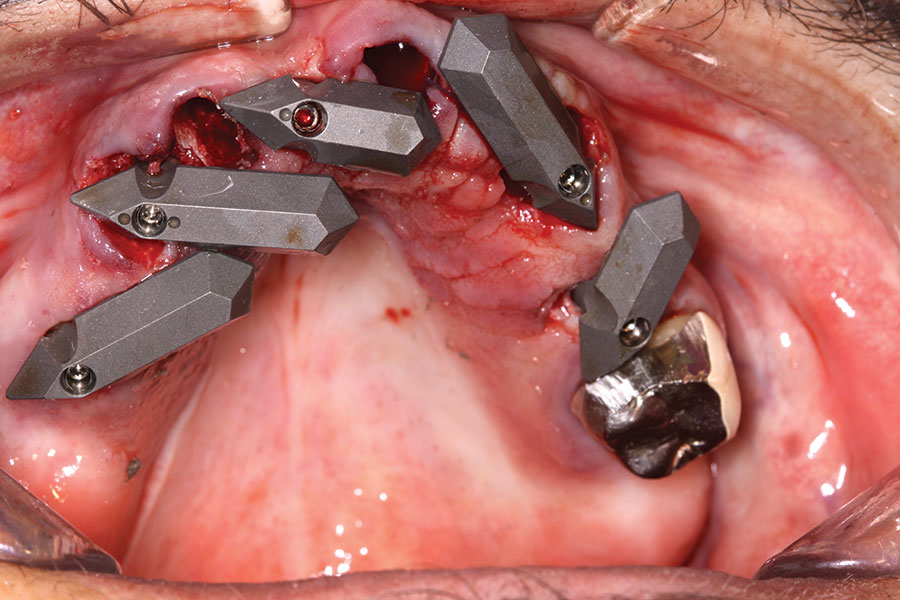

Fig 12. Partial extractions and placement of implants and multi-unit abutments.

Figure 12

Fig 13. Initial scan of scan gauges with residual teeth retained for reference.

Figure 13